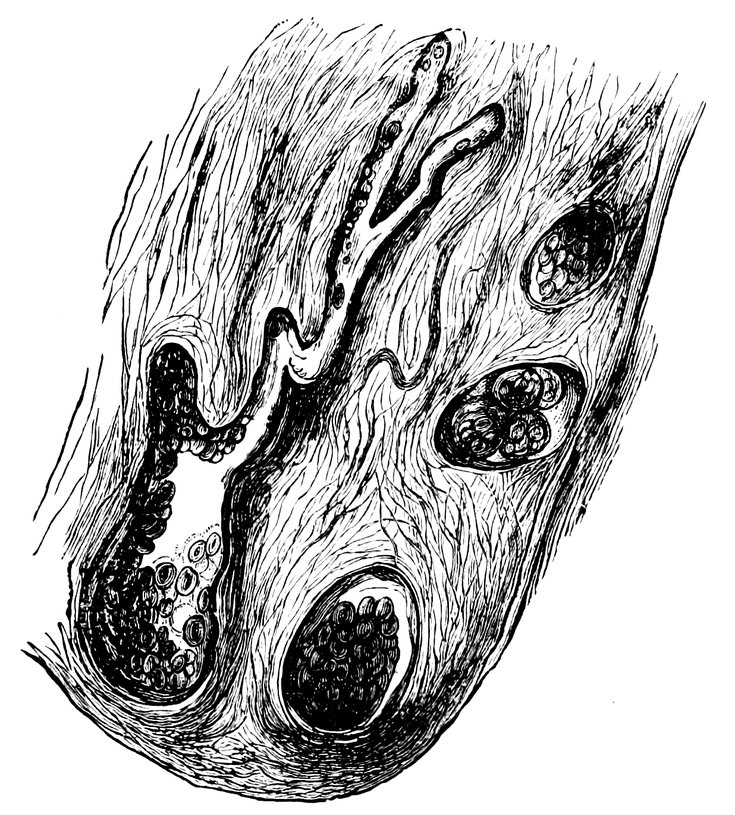

| 84. | Sagittal section through the ovary of a girl aged sixteen | 583 |

| 85. | Sagittal section through the ovary of a woman aged seventy-two years | 584 |

| 86. | Diagrammatic Representation of the Graafian Follicle | 585 |

| 87. | Ovary of a Girl aged nineteen years (Normal Size) | 585 |

| 88. | Ovary of a Woman seventy-two years of age (Normal Size) | 585 |

| 89. | 586 | |

| 90. | 587 | |

| 91. | 588 | |